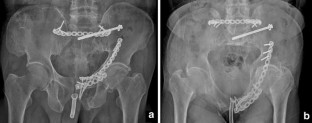

Fig. 2